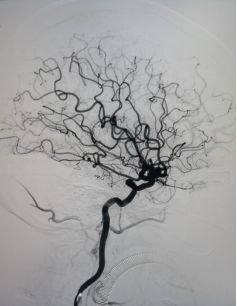

全脑DSA正侧位造影示血流通畅。

术后6个月复查造影示:动脉瘤不显影,血管重建效果令人满意。

术后6个月复查动脉瘤完全闭塞,局部血管重建。